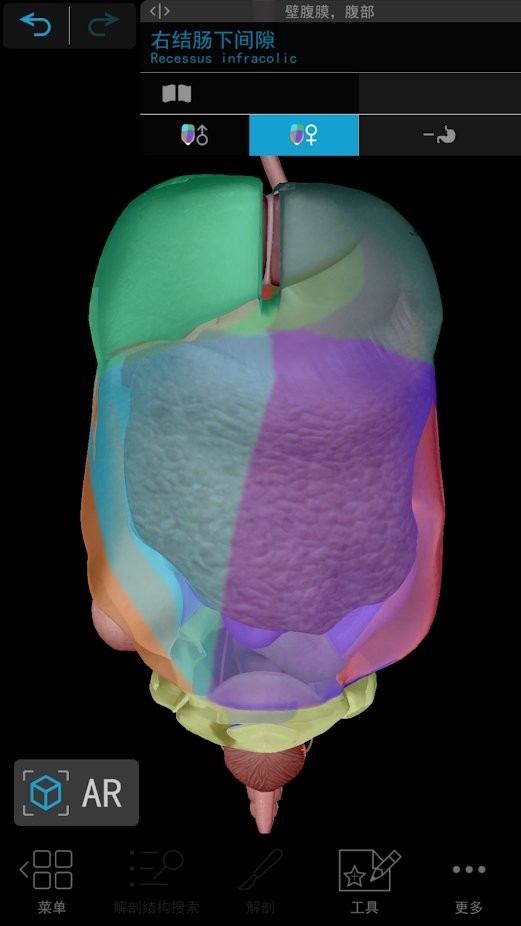

#2021人体解剖图谱 截图